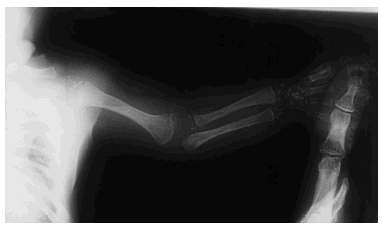

Una serie ósea mostró una displasia espondilopoliepifisaria con punteado de las epífisis de los huesos largos (fig. 1). La radiografía de tórax y las ecografías de abdomen y cerebro fueron por lo demás normales. Las determinaciones analíticas de sangre y orina no mostraron resultados anormales. Se practicó una biopsia cutánea, que mostró una intensa hiperqueratosis ortoqueratósica, con granulosa normal, dilatación comedoniana de los infundíbulos pilosos y focos de calcificación de queratina. El cariotipo fue 46XX.

Fig. 1.--Punteado de las epífisis de los huesos de la extremidad superior.